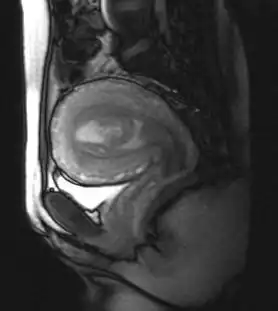

| MRI showing retained products of conception in the first trimester[1] | |